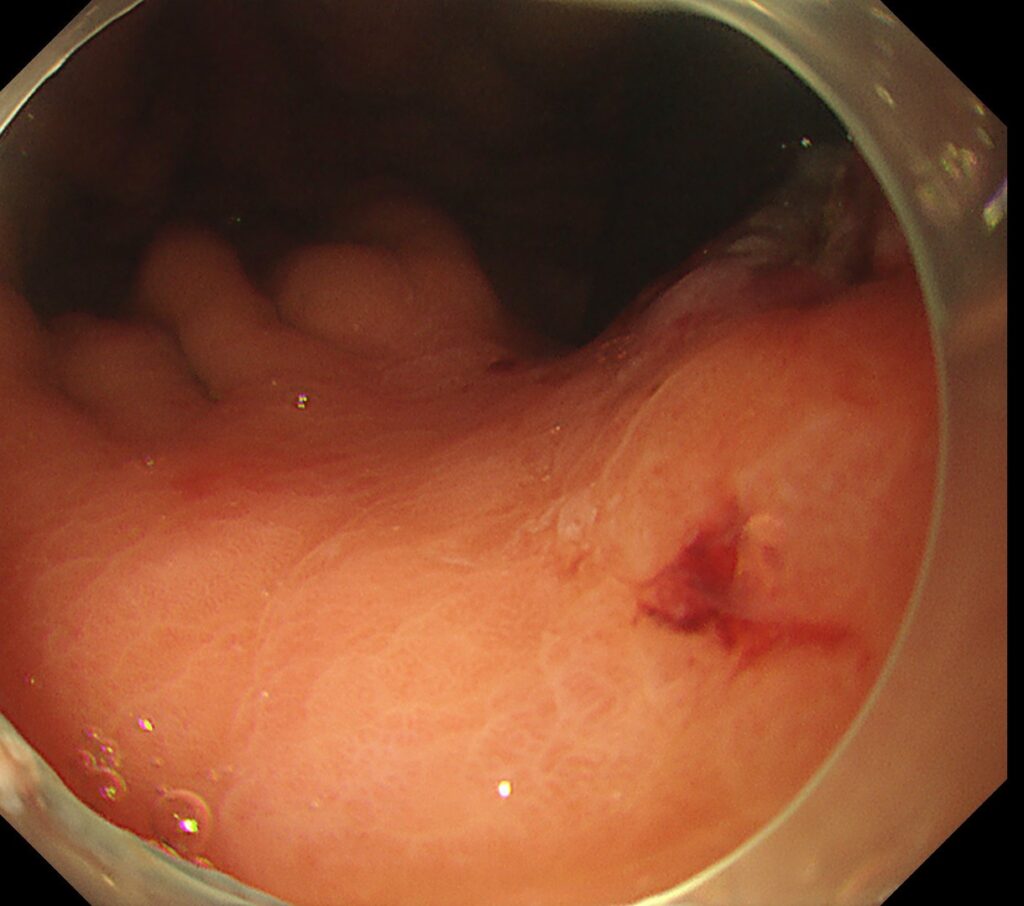

穿通するほどですので、胃は強く変形しており、わかりやすい写真がとれず・・・。

付図のごとく、胃の小彎側に、突如ひだが途絶するほどの潰瘍瘢痕を認めます。

その直上に

易出血性の陥凹性病変を認めます。